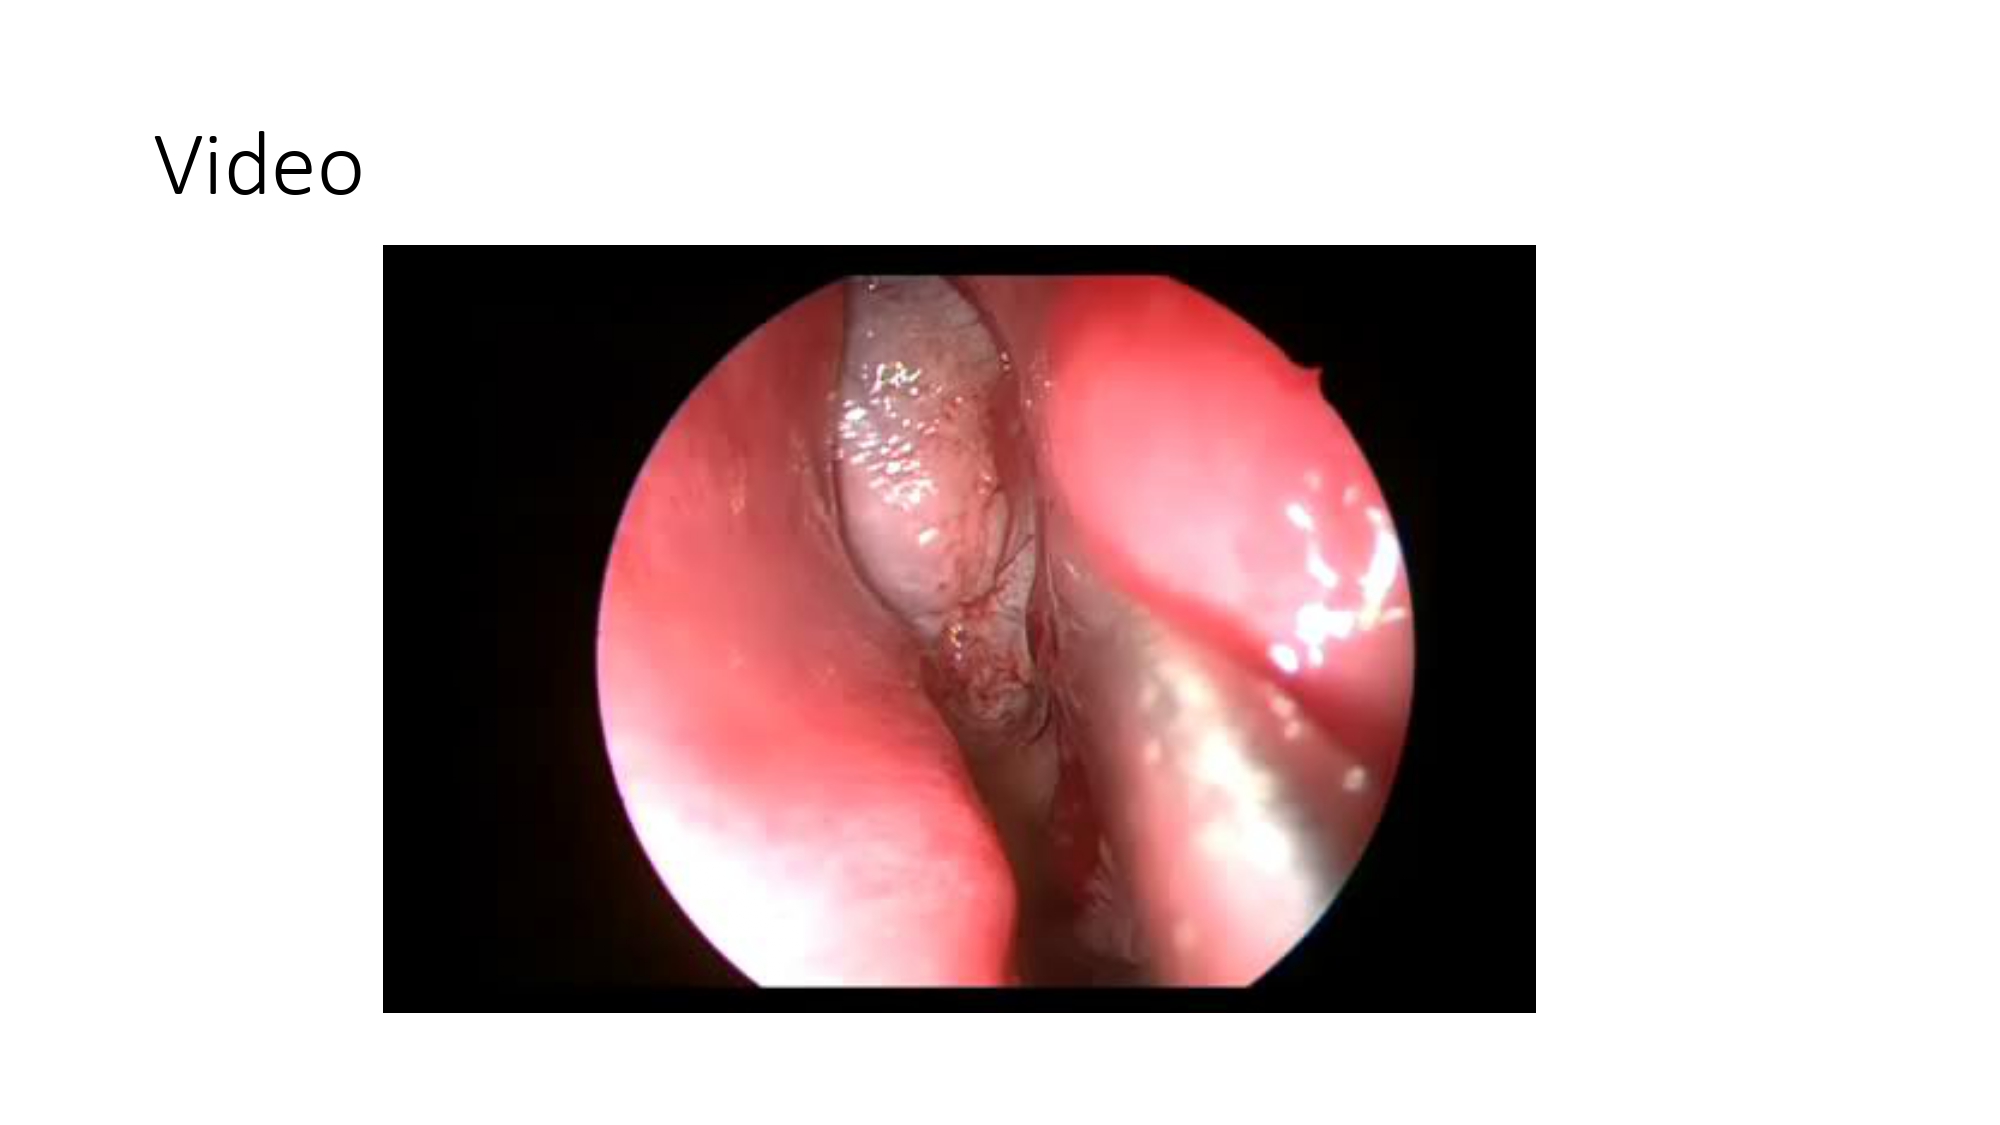

| 15:10 - 16:10 | Interactive Case Demonstration and Discussion II: ~20 minutes each, (5 minutes presentation followed by 15 minutes discussion) Practicals: How I am doing it? Participants present case presentations about how they do it? The faculty comment on and discussion. 1. Endoscopic approach in post-traumatic CSF leakage - Dr. Nguyen Thanh Xuan 2. Endovascular approach in CCF - Assoc. Prof. Le Thanh Dung | Prof. Christian Matula International & local faculties Participants | |